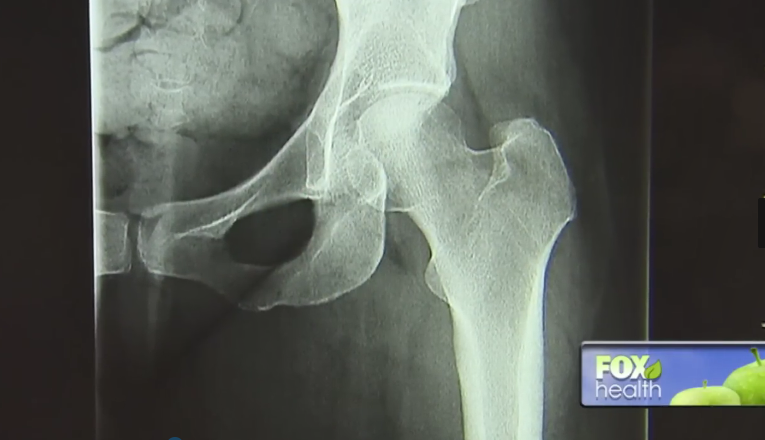

严重的股骨头坏死似乎只能接受髋关节置换术,但再生医学给出了新答案。

股骨头坏死,是一种因骨头“断粮”(血供受损或中断)引发的关节病变,可导致患者股骨头结构改变与塌陷,引起关节疼痛及行走障碍。

这种情况通常需要接受髋关节置换术,该方法始于上个世纪40年代,简单来说就是将受损的髋关节替换为人工假体,美国每年大约有15%的髋关节置换手术都是在拯救股骨头坏死。